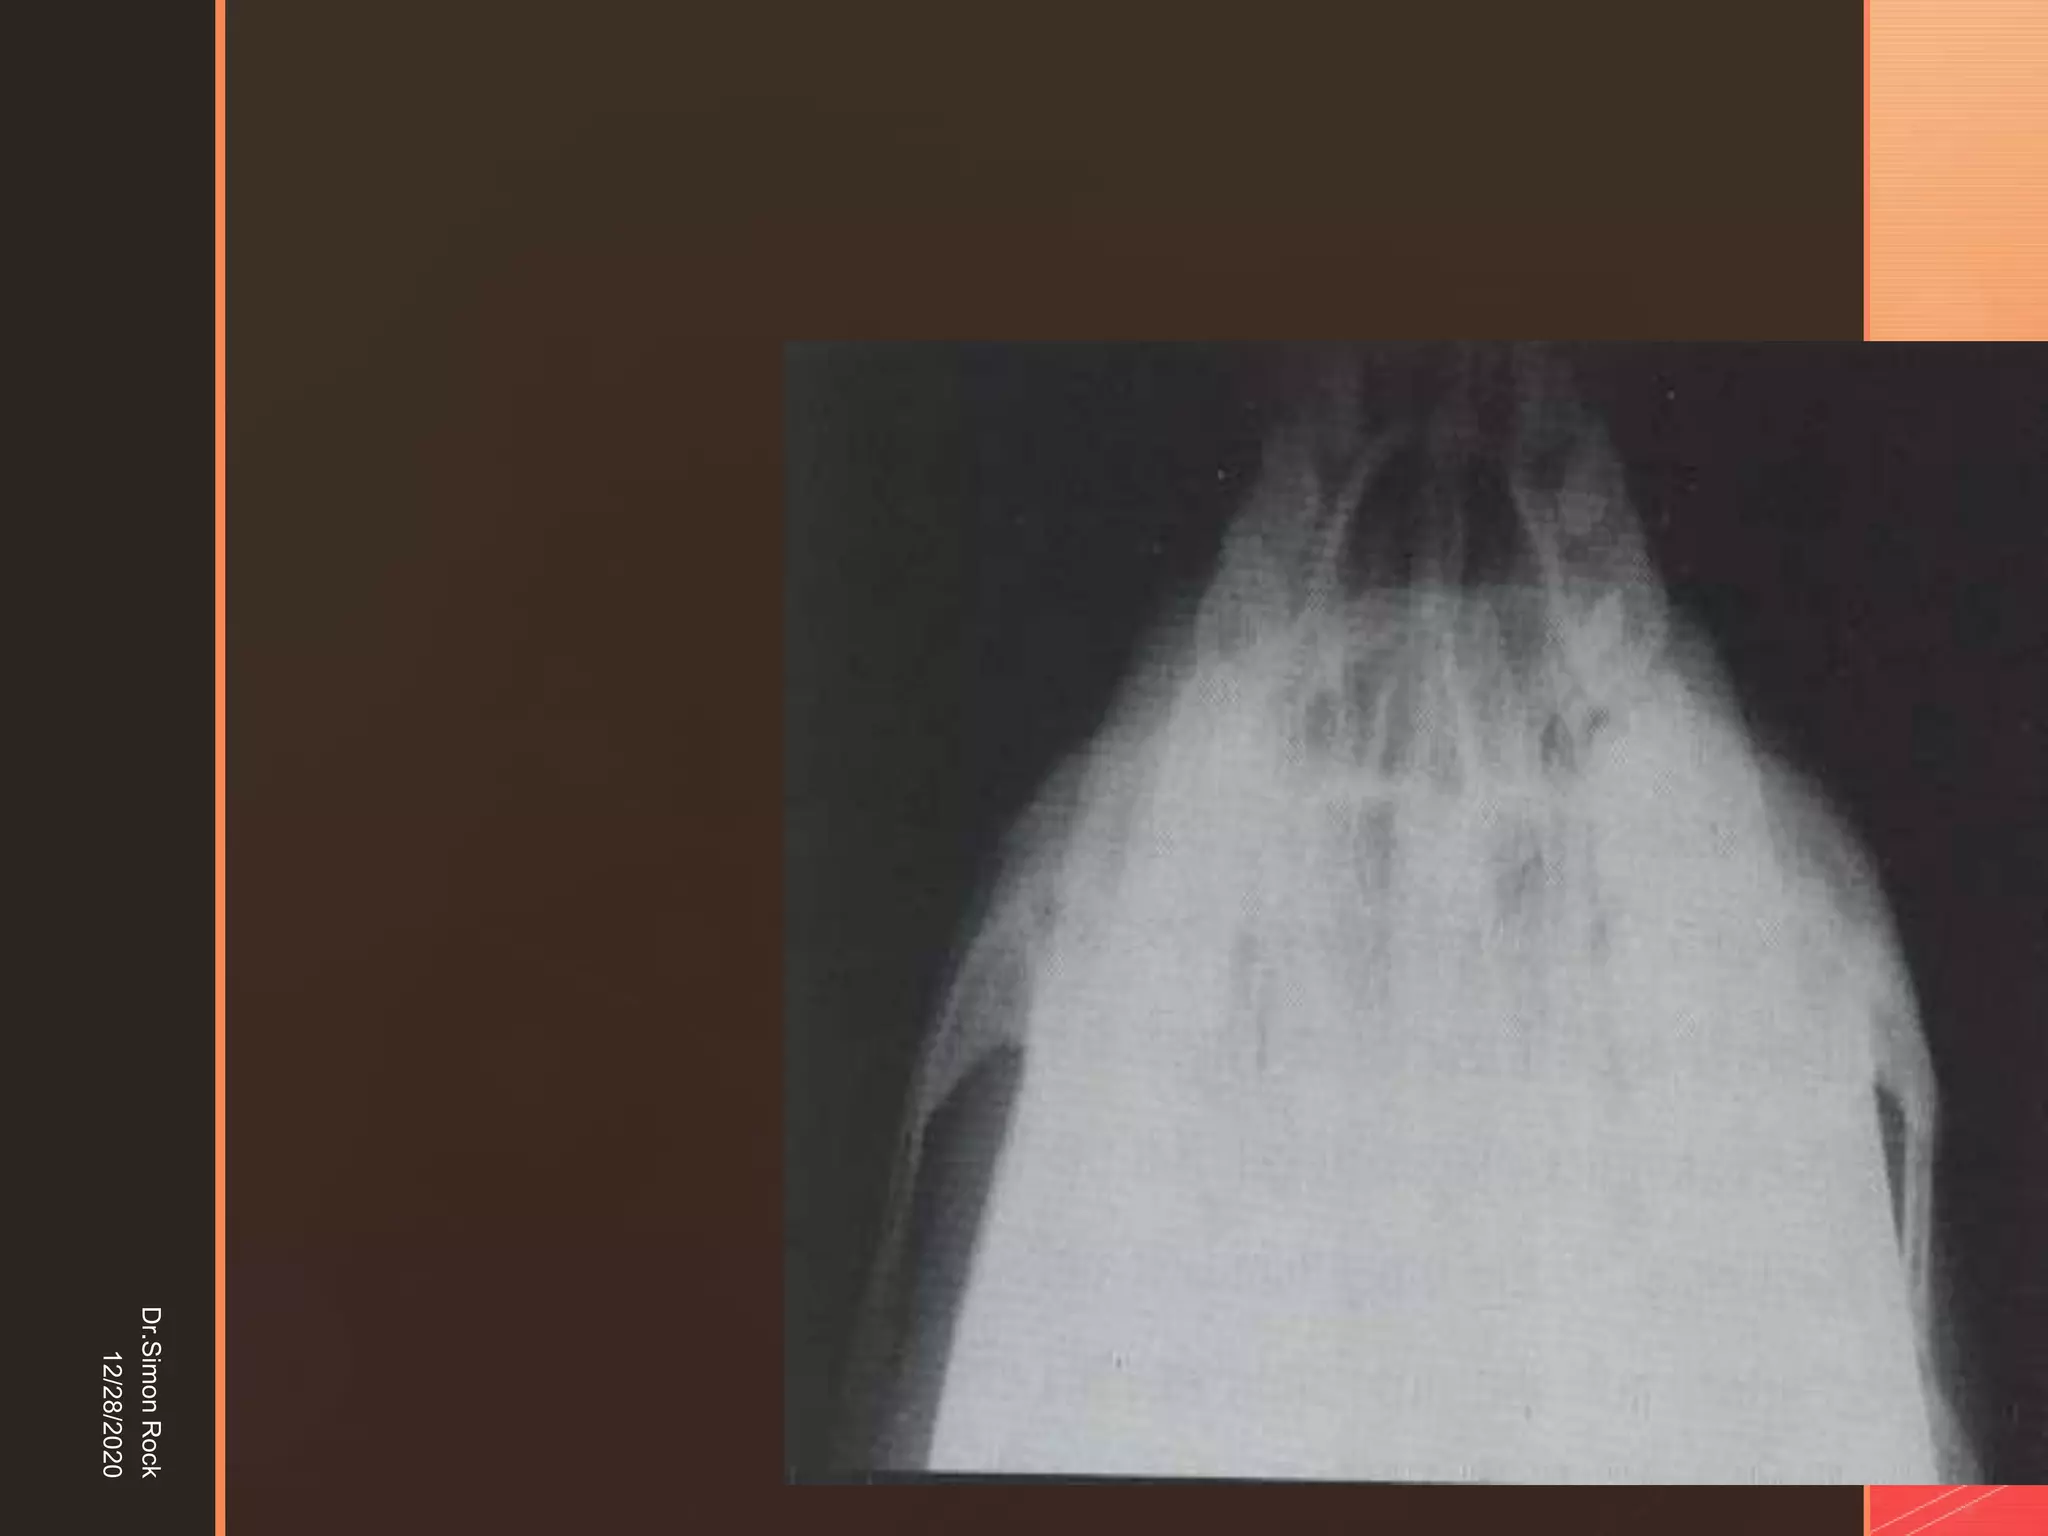

This document discusses the anatomy and fractures of the zygomatic bone. It notes that the zygoma forms the cheekbone and articulates with several other facial bones. Zygomatic fractures most commonly occur in the arch or body due to blunt trauma. Diagnosis involves checking for diplopia, ecchymosis, and other signs of orbital or facial bone involvement. Treatment may involve closed or open reduction based on the severity of displacement. Closed reduction techniques try to elevate the bone back into position without surgery, while open reduction requires surgical exposure and fixation of the fracture site.